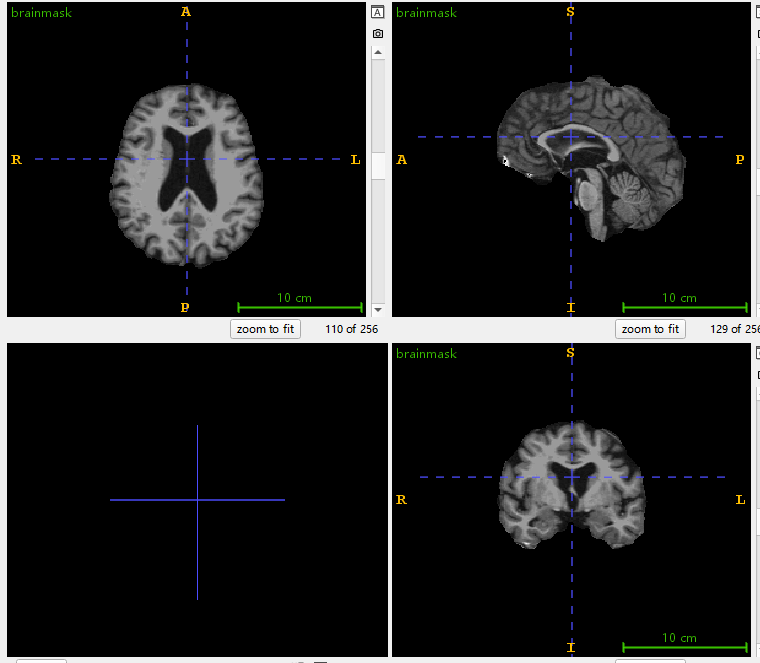

brainmask.nii(我和他们用的brainmask.nii一模一样,这里就放一个了)

仿射配准到MNI152 1mm